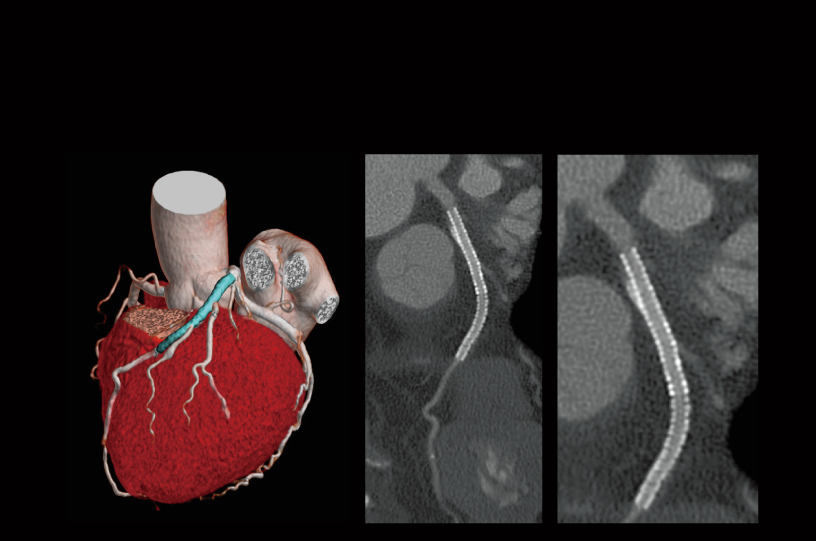

Oclusión aórtica abdominal

Desaturación intraoperatoria de oxígeno (izquierda)

Oclusión de la arteria ilíaca común izquierda (derecha)

- * Las imágenes distintas a las imágenes axia fueron procesadas por el sistema de análisis de imágenes 3D de SYNAPSE 3D.